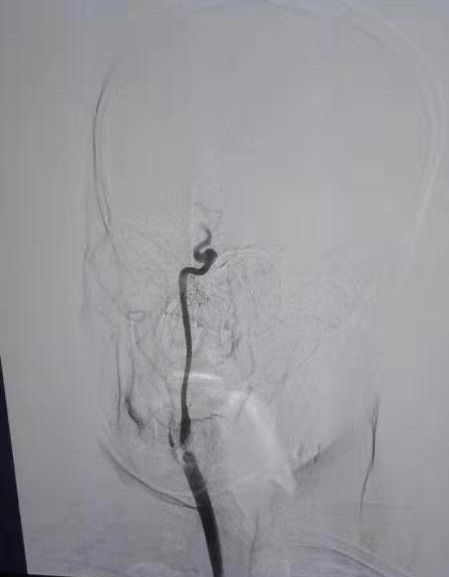

(1)2018年11月1日开展第一例主动脉弓并脑血管造影。

患者:王某 男性  41岁  城关镇